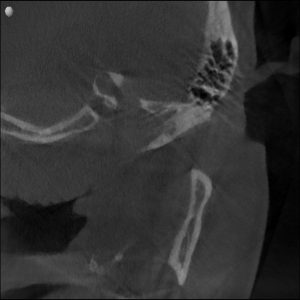

Radiographs confirmed it — his airway was constricted.

His jaw alignment had shifted to make breathing easier, but that adaptation had caused years of TMJ dysfunction.

Clinical & Radiographic Findings

- Muscular hyperactivity in the masseter and temporalis

- Clicking and fatigue during jaw movement

Radiographs confirmed increased airway space and balanced joint position.